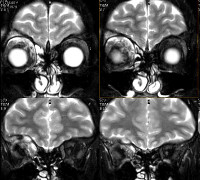

Диагностика псевдотумора орбиты основывается на анамнестических данных, результатах наружного осмотра и пальпации, офтальмоскопии, визиометрии, компьютерной томографии (КТ), гистоморфологического и цитологического исследования. При помощи компьютерной томографии удается провести дифференциальную диагностику онкологического процесса с псевдотумором орбиты. На КТ орбит визуализируются расширенные экстраокулярные мышцы, определяются неровность контура по всей длине. Мышечная ткань, как правило, повышенной плотности и прилегает к клетчатке, расположенной в ретробульбарном пространстве. При первичном идиопатическом миозите визометрия позволяет оценить степень снижения остроты зрения. В ходе офтальмоскопии обнаруживается застойный диск зрительного нерва с признаками атрофии.

Методом пальпаторного исследования при дакриоадените определяется плотная подвижная ткань с гладкой поверхностью в зоне проекции слезной железы. Для дифференциации данного вида псевдотумора орбиты с эпителиальной опухолью необходимо проведение тонкоигольчатой аспирационной биопсии с последующим цитологическим исследованием пунктата. При микроскопическом исследовании мазка в случае дакриоаденита визуализируются лимфоциты, плеоморфные клетки и фрагменты волокнистой ткани. Методом КТ определяется повышение плотности тканей, окружающих псевдотумор орбиты, совместно с увеличением размера слезной железы.

В случае васкулита как одного из проявлений псевдотумора орбиты при офтальмоскопии можно выявить застойный диск зрительного нерва. При этом данные визиометрии указывают на снижение остроты зрения. На КТ визуализируются участки повышенной плотности с четким ровным контуром, которые не прилежат к мышечной ткани и зрительному нерву. В случае склеротических изменений ретробульбарная клетчатка имеет вид неоднородной ткани высокой плотности с нечеткими границами и вовлечением в патологический процесс оптического нерва.